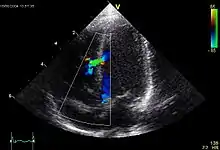

| .jpg.webp) Echokardiogramm eines ASD II, d.h. Ostium-secundum-Typ. |

Atrial septal defect (ASD)

ASD II:

Das heruntergewachsene Septum primum reisst normalerweise in der Mitte ein und bildet das Foramen secundum bzw. Foramen ovale. Dieses wird durch das links vom Septum primum ebenfalls von oben herunterwachsende Septum secundum gardinenartig bedeckt (Ventil) und kurz nach der Geburt durch Umkehr der Druckverhältnisse funktionell (z.T. strukturell durch Verklebung) verschlossen. Ist der Verschluss so ungenügend, dass es zum Links-rechts-Shunt kommt, spricht man vom offenen Foramen ovale bzw. ASD II. Der ASD II ist im Ggs. zum ASD I weiter oben lokalisiert. Er macht oft wenig Symptome und wird oft erst im Erwachsenenalter erkannt. Der Links-Rechts-Shunt kann im EKG zu Zeichen der Rechtsherzbelastung führen (Rechtslagetyp, P pulmonale, inkompletter Rechtsschenkelblock ohne Hypertrophie-Zeichen (rsr's') als Zeichen der rechtsventrikulären Volumenbelastung) und bei starker Ausprägung zu klinischen Symptomen führen.

|  Echokardiogramm eines VSD. |